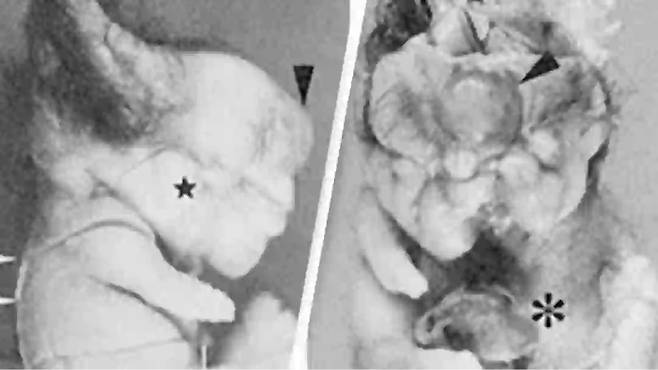

종양 속에는 머리카락, 이빨, 피부, 연골조직은 물론, 사지처럼 보이는 돌출 구조와 눈 조직까지 포함돼 있었던 겁니다.

해당 사례는 기형종(teratoma), 즉 여러 신체 조직이 섞여 자라는 종양으로 밝혀졌습니다.

기형종은 배아세포에서 발생하는 종양으로, 뇌조직, 치아, 턱, 근육, 모발, 심지어 망막 조직까지 포함될 수 있습니다.

의료진은 해당 여성의 종양을 절제했고, 조직 검사 결과 성숙 기형종으로 최종 진단됐습니다.